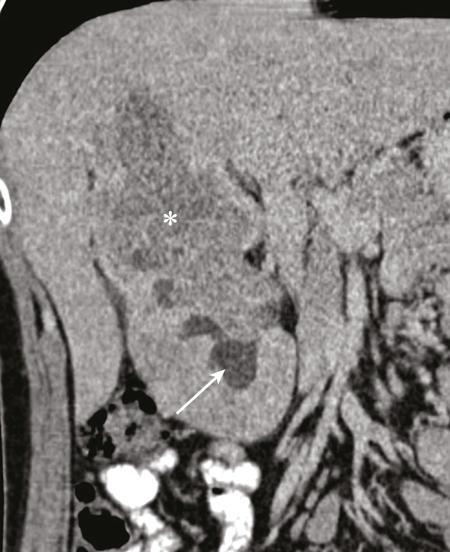

IMAGING OF RENAL MALIGNANCIES IN ADULTS Aparna Katdare, Palak Bhavesh Popat, Nilesh P. Sable, Ganesh Bakshi, Suyash Kulkarni Detection of renal masses has increased remarkably in recent times owing to wide-spread use of cross-sectional imaging. Imaging plays an important role in characterizing renal masses and is indispensable in treatment planning in renal malignancies. The most commonly encountered malignant renal masses in practice include renal cell carcinoma (RCC), urothelial carcinoma, lymphoma and metastases. Urothelial carcinoma and lymphoma have been covered in detail in separate chapters. RCC constitutes nearly 90% of all renal malignancies with a higher incidence in North America and Europe than India, Africa and China. With an increase in the number of cross-sectional studies performed, especially in Western population, the incidental diagnosis of RCC has increased in recent times, with such incidentally diagnosed lesions presenting at earlier stages with better prognosis and reduced rates of recurrence. The median age of presentation of RCC is 64 years according to the Surveillance, Epidemiology and End Results (SEER) program database and almost a decade earlier in Indian population, with a definite increasing risk of RCC with increasing age. Males are affected about 2–3.5 times more than females. In the Indian population, patients have been seen to present at a later stage as compared to the Western population. Amongst the various postulated risk factors, there is convincing evidence that smoking, hypertension, obesity and acquired renal cystic disease increase the risk of RCC. Alcohol intake and physical activity have been found to be associated with reduced risk of RCC. Trichloroethylene and cadmium exposure have been postulated as likely causes as well. Two to four per cent of RCCs are hereditary, with association of various genetic disorders such as Von Hippel Lindau (VHL) syndrome, hereditary papillary renal carcinoma, hereditary leiomyomatosis RCC, Birt-Hogg-Dube syndrome, chromosome 3 translocation and tuberous sclerosis (TCS1, TCS2). The WHO classification of 2016 (Table 11.25.1.1) stratifies tumours of the kidney into different subtypes based on cytoplasmic and architectural features, tumour location, background renal disease and molecular alterations. Clear cell renal cell carcinoma Multilocular cystic renal neoplasm of low malignant potential Papillary renal cell carcinoma Hereditary leiomyomatosis and renal cell carcinoma-associated renal cell carcinoma Chromophobe renal cell carcinoma Collecting duct carcinoma Renal medullary carcinoma MiT family translocation renal cell carcinomas Succinate dehydrogenase-deficient renal carcinoma Mucinous tubular and spindle cell carcinoma Tubulocystic renal cell carcinoma Acquired cystic disease-associated renal cell carcinoma Clear cell papillary renal cell carcinoma Renal cell carcinoma, unclassified Papillary adenoma Oncocytoma 8310/3 8316/1a 8260/3 8311/3* 8317/3 8319/3 8510/3a 8311/3a 8311/3 8480/3a 8316/3a 8316/3 8323/1 8312/3 8260/0 8290/0 Metanephric adenoma Metanephric adenofibroma Metanephric stromal tumour 8325/0 9013/0 8935/1 Nephrogenic rests Nephroblastoma Cystic partially differentiated nephroblastoma Paediatric cystic nephroma 8960/3 8959/1 8959/0 Clear cell sarcoma Rhabdoid tumour Congenital mesoblastic nephroma Ossifying renal tumour of infancy 8964/3 8963/3 8960/1 8967/0 Leiomyosarcoma Angiosarcoma Rhabdomyosarcoma Osteosarcoma Synovial sarcoma Ewing sarcoma Angiomyolipoma Epithelioid angiomyolipoma Leiomyoma Haemangioma Lymphangioma Haemangioblastoma Juxtaglomerular cell tumour Renomedullary interstitial cell tumour Schwannoma Solitary fibrous tumour 8890/3 9120/3 8900/3 9180/3 9040/3 9364/3 8860/0 8860/1a 8890/0 9120/0 9170/0 9161/1 8361/0 8966/0 9560/0 8815/1 Cystic nephroma Mixed epithelial and stromal tumour 8959/0 8959/0 Well-differentiated neuroendocrine tumour Large cell neuroendocrine carcinoma Small cell neuroendocrine carcinoma Phaeochromocytoma 8240/3 8013/3 8041/3 8700/0 Renal haematopoietic neoplasms Germ cell tumours The morphology codes are from the International Classification of Diseases for Oncology (ICD-O) {917A}, Behaviour is coded/0 for benign tumours; /1 for unspecified, borderline or uncertain behaviour; /2 for carcinoma in situ and grade III intraepithelial neoplasia; and /3 for malignant tumours. The classification is modified from the previous WHO classification (756A), taking into account changes in our understanding of these lesions. aNew code approved by the IARC/WHO Committee for ICD-O. Of these, the most common entity is the clear cell subtype, while papillary and chromophobe subtypes are less common. The different subtypes show varied biological behaviour, treatment response and prognosis. The 2017 guidelines by American Urological Association (AUA) as well as 2019 guidelines by European Society of Medical Oncology (ESMO) recommend multiphase cross-sectional imaging by either CT or MRI for renal mass characterization and staging. AUA 2017 guidelines recommend renal mass characterization on the basis of tumour complexity, contrast enhancement and presence or absence of fat. MRI has an upper hand over CT in characterizing subtle mass enhancement, cystic lesions and lesions less than 2 cm. ESMO recommends contrast-enhanced CT study of the chest, abdomen and pelvis for renal mass staging. Bone scan and brain CT or MRI can be considered if indicated by clinical or laboratory investigations. For characterization of renal masses, a multiphase CT or MRI study is recommended. CT study constitutes an unenhanced study followed by contrast injection and acquisition of corticomedullary phase at 40 seconds, nephrographic phase at around 100 seconds and delayed phase at around 5 minutes. MRI protocol includes T2-weighted single-shot fast spin-echo 2D sequences, axial T1-weighted 2D sequence with in-phase and opposed-phase gradient echo imaging, precontrast and postcontrast imaging with a 3D T1-weighted spoiled gradient recalled sequences in corticomedullary phase at 30 seconds, nephrographic phase at 100 seconds, 180–210 seconds and delayed phase imaging at 5 minutes and diffusion-weighted imaging with multiple b-values 0–50, 400–500 and 800–1000 s/mm2. The ACR White Paper on CT imaging of incidental renal mass recommends using the following descriptors for characterizing renal masses: Given the prognostic implications, it is worthwhile for radiologists to know the imaging features that may help discriminate between the common histological subtypes of RCC on various imaging modalities. This is the most common histological type of RCC, accounting for about 70% of cases. These are exophytic tumours with a heterogeneous appearance due to the presence of necrosis, intratumoural haemorrhage, cystic components with septations and calcific foci and hence have a more heterogeneous appearance on cross-sectional imaging than the other subtypes (Fig. 11.25.1.1). Necrosis is seen more often in larger masses and higher tumour grades (Fig. 11.25.1.2). On CT, depending on the tumour composition, these are seen as heterogeneous lesions, show marked contrast enhancement in the corticomedullary phase with washout on nephrogenic phase (Fig. 11.25.1.2). On MRI, these characteristically show high signal intensity on T2W sequences (Fig. 11.25.1.3). The presence of intracytoplasmic fat in the clear cells of the tumour is reflected in the loss of signal in opposed phase images on chemical shift imaging, which is seen in nearly 60% of these tumours. A pseudocapsule may be seen, which is best appreciated on T2-weighted imaging on MRI; the presence of a pseudocapsule has a high negative predictive value for perinephric extension (Figs. 11.25.1.3 and 11.25.1.4). Conversely, larger tumours with higher grades often have interrupted pseudocapsule and hence tend to be irregular, spread into the perinephric fat with renal vein and inferior vena cava (IVC) invasion (Figs. 11.25.1.5 and 11.25.1.6). On diffusion-weighted imaging, clear cell RCCs have been seen to have higher ADC values than nonclear cell RCCs, and lower-grade tumours have been seen to have higher ADC values than higher-grade tumours. The clear cell variant has worse prognosis than the papillary and chromophobe subtypes, presenting at a more advanced stage and being more likely to recur or metastasize (Fig. 11.25.1.7), with lower 5-year survival rates at 44%–69% as compared to 78%–92% for the other two. Papillary RCC comprises about 10%–15% of RCCs. These are slow-growing tumours and hence are well-marginated in contrast to clear cell RCC. As they are hypovascular, their enhancement on CT is significantly less than clear cell RCC (Fig. 11.25.1.8). These show characteristically low signal on T2W images on MRI (Fig. 11.25.1.9). Intracytoplasmic or macroscopic fat is less often seen on MRI imaging as compared to the clear cell variants. Larger tumours tend to be more heterogeneous (Fig. 11.25.1.10). These tumours may sometimes show cystic appearances, mural projections or blood degradation products. Calcifications are more common in papillary variants than clear cell RCC. Multifocality and bilaterality are also more common in these tumours than clear cell variants. These account for about 5% of RCCs. These are less aggressive, more homogeneous and hypovascular lesions than clear cell variants, with intensity of contrast enhancement on cross-sectional imaging being midway between clear cell and papillary variants. They show low to intermediate T2 signals on MRI. A characteristic feature is the presence of a central scar and spoke-wheel enhancement, the latter being a histopathological and imaging similarity between these tumours and oncocytoma (Fig. 11.25.1.11). Other subtypes of RCC are much less common but some may show distinct imaging findings. Multilocular cystic RCCs have excellent prognosis and lack mural nodules within the cystic components, unlike clear cell RCCs with cystic degeneration which show mural nodules. Collecting duct carcinomas, on the other hand, are aggressive tumours with poor prognosis and have medullary origin, and therefore appear similar to transitional cell carcinomas on imaging. Medullary RCCs are associated with sickle cell disease and sickle cell trait and are seen as infiltrating intracalyceal obstructive lesions with associated nodal disease. The imaging work-up of a suspected RCC is aimed at: Localized renal cancer is defined as a disease confined to the renal capsule and refers mainly to stage I and II disease. Nearly 70% of RCCs, especially the lower-stage lesions, are incidentally diagnosed on cross-sectional imaging. Also, amongst incidentally diagnosed renal lesions less than 4 cm in size, about 20% turn out to be benign on histopathology. Asymptomatic incidentally diagnosed small renal masses have an indolent course and better prognosis. Nephron-sparing surgery (NSS) has gathered momentum in recent years due to promising results and prognoses in small lesions. The 2017 AUA guidelines for localized renal masses describe restricted and well-defined indications for radical nephrectomy, bigger role of nephron-sparing procedures such as partial nephrectomy, tumour enucleation and thermal ablation, as well as increasing role for biopsy as well as active surveillance of such lesions. Hence, imaging findings in these lesions become critical in charting management of these patients. The imaging features of common histopathological subtypes of RCCs have already been discussed above. Signal intensity on T2W images and corticomedullary phase enhancement have been seen to be independent predictors of clear cell and papillary RCCs. Further, T2 signal homogeneity can be a predictor for slower growth rate. Hence, in general, multiparametric MRI studies have been shown to be effective in small renal mass characterization and can subsequently guide decisions regarding biopsy, surgery or surveillance. CT is a good alternative in patients with contraindication to MRI. For cystic renal lesions, the Bosniak classification, which stratifies the risk of neoplasia in cystic renal lesions based on the complexity of their appearance (wall thickness, septations, solid component), can be used effectively to decide further course of management. The Bosniak classification originally applies to CT findings but can logically be extrapolated to MRI, USG and Contrast Enhanced Ultrasound (CEUS) as well. Bosniak I and II cysts are benign while Bosniak IIF, III and IV cysts show progressively increasing risk of neoplasia. Given the more indolent course of cystic RCCs as compared to solid lesions and possible complications of interventions, lately there has been a case for even the type III and IV cysts, which previously would be operated, to be followed up, especially if patient has existing comorbidities or if the solid component is minimal. Initial follow-up would be at 6 months, followed by annual imaging. AUA 2017 guidelines recommend considering renal mass biopsy if haematologic, metastatic, inflammatory or infectious aetiology is suspected. Once the need for surgery is established in a localized disease, NSS may be considered for stage Ia and Ib disease. To predict perioperative outcomes in NSS, various scoring systems have been proposed for preoperative renal mass evaluation, such as R.E.N.A.L. nephrometry score, PADUA score (Preoperative aspects and dimensions used for anatomical classification), C-index method and mathematical tumour contact surface area (CSA). The popular R.E.N.A.L. nephrometry score takes into account various tumour descriptors that help decide the technical feasibility of NSS and predict surgical outcomes. These include tumour radius, exo/endophytic location, nearness to collecting system or renal sinus, anterior/posterior location and location with reference to polar lines. These descriptors need to be commented upon diligently while reporting renal masses (Table 11.25.1.4). Higher scores are seen to correlate with ischaemia time, postoperative urologic complications, higher grade and mortality. These include organ-confined tumours more than 7 cm in size, or tumours of any size which show regional nodal involvement and/or invasion of perinephric tissues but confined to Gerota’s fascia. These include renal vein and IVC invasion (luminal and mural). Generally, radical nephrectomy is recommended by the National Comprehensive Cancer Network (NCCN) in stage II and III RCCs. Both CT and MRI are effective in diagnosing locally advanced disease in RCC. The loss or interruption of pseudocapsule is seen in more infiltrative and aggressive disease and is best seen on MRI. Local infiltration may be in the form of contiguous spread to perinephric tissues or discrete deposits in perinephric fat (Fig. 11.25.1.15). IVC or renal vein invasion could be in the form of intraluminal thrombosis or invasion of the vessel wall and have implications on surgical approach and outcomes. Tumour thrombus can be distinguished from bland thrombus by confirming vascularity within the thrombus on imaging. Doppler evaluation, CEUS, CT and MRI can all be helpful for the same. MRI is better than other modalities for venous evaluation, especially for mural invasion and IVC invasion (Figs. 11.25.1.16 and 11.25.1.17). Right-sided tumours, anteroposterior IVC diameter of 2.4 cm or more at the level of renal hilum and complete IVC occlusion at this level are associated with higher risk of IVC resection. About 16% of patients with RCC have metastases at diagnosis and about 20%–30% of patients operated for local disease develop recurrence or metastases at a later date. The recurrent disease occurs most commonly within 3 years of diagnosis and uncommonly even later in young patients or large tumours. The most common sites of metastases from RCC are lungs, liver, bones, nodes, adrenals and brain. CT scan is the preferred modality for primary staging and surveillance for metastases because of its widespread availability and versatility for diagnosing bone and soft tissue lesions. MRI is preferred for looking for recurrence in postablative lesions, wherein these are seen as new enhancing lesions or show increase in the size of preexisting enhancing components. 18FFluorodeoxyglucose – Positron Emission Tomography (PET)/CT and PET/MRI may be helpful to look for metastatic disease as well. 18FSodium fluoride – PET/CT has been found to be better than CT and bone scan in detecting osseous metastases. RCC is a relatively radiation-resistant tumour, and treatment options tilt in favour of surgical procedures for localized and locally advanced diseases. For metastatic disease, post-risk assignment, the treatment has to be planned. Treatment can be offered as per size and the clinical stage.